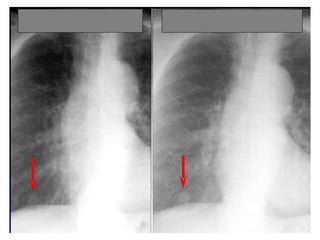

Pulmonary infarction

Chest radiograph with ‘classical’        Chest X ray after 4 days, prior

appearance of a pulmonary infarction –   to treatment, showing massive

a wedge-shaped lesion peripherally set   increase in volume of lesion.

against the pleura